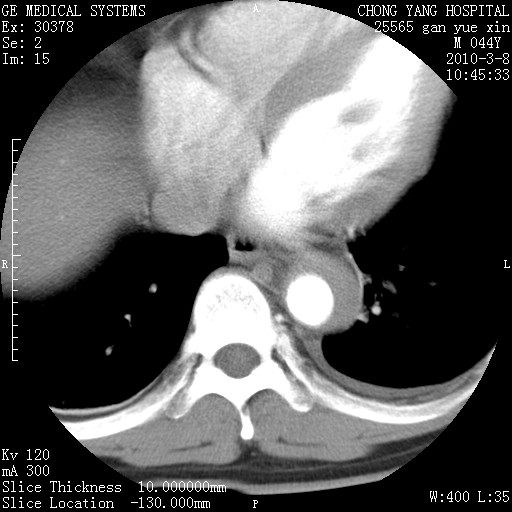

标题: CT24940:主动脉增强,典型病例。 [打印本页]

标题: CT24940:主动脉增强,典型病例。

夹层动脉瘤。

动脉夹层

夹层动脉瘤,典型

主动脉夹层。

动脉夹层的分型:

⒈debakey分型:根据主动脉夹层累及部位,分为三型:ⅰ型:原发破口位于升主动脉或主动脉弓部,夹层累及升主动脉、主动脉弓部、胸主动脉、腹主动脉大部或全部,少数可累及髂动脉。ⅱ型:原发破口位于升主动脉,夹层累及升主动脉,少数可累及部分主动脉弓。ⅲ型:原发破口位于左锁骨下动脉开口远端,根据夹层累及范围又分为ⅲa,ⅲb。ⅲa型:夹层累及胸主动脉。ⅲb型:夹层累及升主动脉、腹主动脉大部或全部。少数可累及髂动脉。

⒉stanford分型:a型:夹层累及升主动脉,无论远端范围如何。b型:夹层累及左锁骨下动脉开口以远的降主动脉。

夹层动脉瘤,少量胸水

夹层动脉瘤;左侧少量胸腔积液。

典型主动脉夹层。